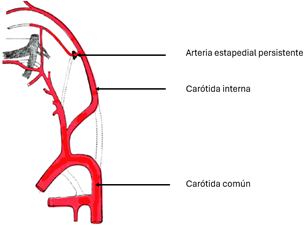

Arteria estapedial persistente

La arteria estapedial persistente (ASP) es un vaso pequeño anormal que surge de la porción petrosa de la arteria carótida interna y atraviesa el oído medio. Es el resultado de la falla de la regresión de la arteria estapedial embrionaria. La prevalencia varía entre el 0,02 y el 0,48% en la población general (Fig. 10-12).

Figura 11. Arteria estapedial (flecha amarilla) y porción petrosa de carótida (líneas rojas) |

Figura 12. Arteria estapedial persistente |